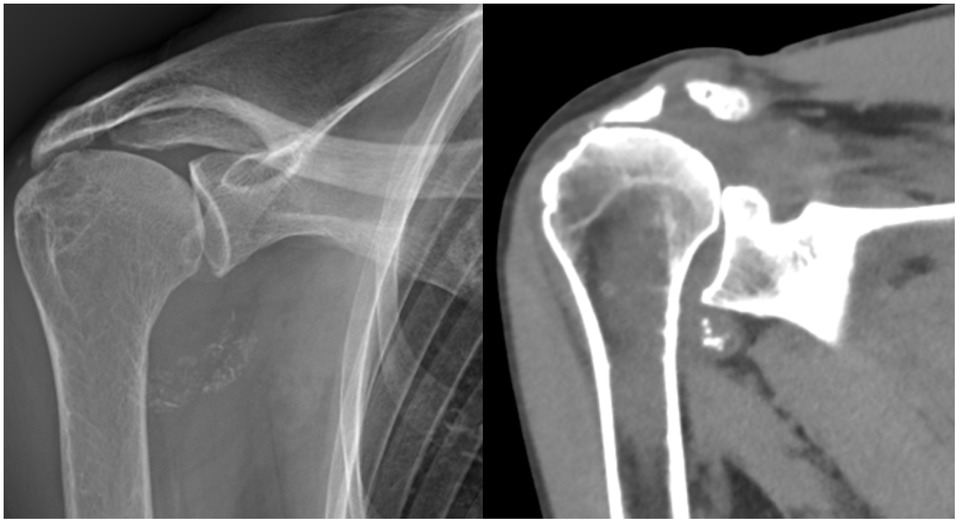

A 78-year-old woman presented with a one-year history of recurrent, debilitating pain and swelling in her right shoulder, without prior trauma. She reported three distinct episodes of acute pain with complete resolution between episodes. Physical examination revealed tenderness in the axillary recess, pain on abduction beyond 60 degrees, and a positive Neer impingement test. Laboratory tests including erythrocyte sedimentation rate (ESR) (12 mm/h), CRP (0.4 mg/dL), serum calcium, parathyroid hormone, and ferritin were within normal limits. Radiographs and CT scans showed dense, well-defined calcifications in the axillary pouch and within the supraspinatus muscle belly, highly atypical sites for crystal deposition (Figures 1 and 2). Joint aspiration was attempted but was not feasible due to the location of the effusion.

X-ray (left) and computed tomography (CT) scan (right) of the right shoulder showing well-defined calcifications in the axillary recess.

This case highlights the diagnostic challenge of atypical presentations and the utility of the new classification criteria in guiding diagnosis when definitive crystal diagnosis is unobtainable. The calcifications in the axillary recess and intramuscular location within the supraspinatus muscle qualified for the highest imaging score (23 points for “atypical calcifications”) based on the consensus definitions established by Tedeschi et al.[9] which specify that periarticular and intramuscular deposits represent atypical features distinct from typical cartilaginous chondrocalcinosis.